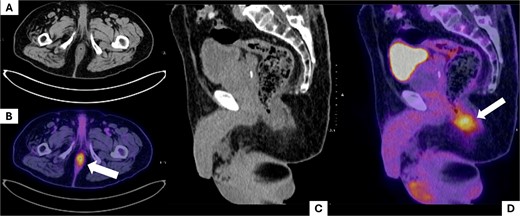

A positron emission tomography (PET-CT) scan demonstrated heightened metabolic activity at the level of the anal canal, without evidence of suspicious lymph nodes or distant metastases (Fig. 1). Surgical exploration of the anal canal revealed a hyperpigmented tumor-like lesion originating from the anal canal and involving the anterior quadrants of the perianal skin (Fig. 2). Subsequently, a wide local excision of the lesion was performed (Fig. 3). Histopathological examination confirmed the diagnosis of a poorly differentiated invasive nodular melanoma, measuring 3.3 × 2.8 cm, with a Clark level of IV and a Breslow depth of 6 mm (Fig. 4). The patient experienced an uneventful postoperative course and was discharged for follow-up and immunotherapy management in the outpatient medical oncology clinic.

Positron emission tomography (PET-CT) scan. The images show the region corresponding to the anal canal. A and B show the affected anatomical region in axial slices. (A) Shows the anal canal with slight asymmetrical thickening predominantly on the left side, with no suspicious adenopathies; (B) shows uptake corresponding to the increase in local metabolism secondary to the tumor lesion (white arrow). C and D show sagittal slices of the pelvic region, where uptake is observed at the level of the anal canal (white arrow).